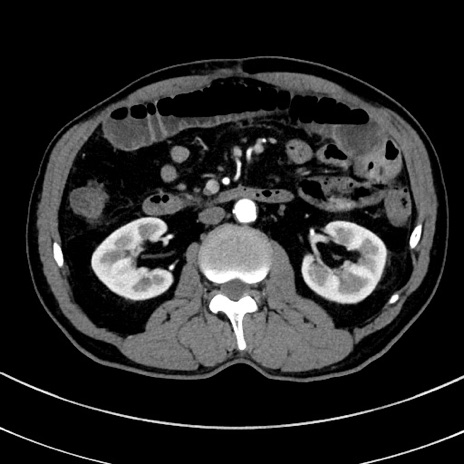

症例8(横断像)

【症例】 60歳代男性

【主訴】 黒色吐物

【現病歴】 4日前から嘔気自覚、2日前の朝食後にも嘔気あり、自分で手で嘔吐反射起こし嘔吐したところ血が混ざっていたため受診。

【既往歴】 5年前汎発性腹膜炎を伴う急性虫垂炎で手術、高血圧、前立腺肥大症、高脂血症

【身体所見】 腹部正中に手術癩痕あり 腹部平坦・軟圧痛なし膨満感あり

【データ】WBC 8400、CRP 4.54